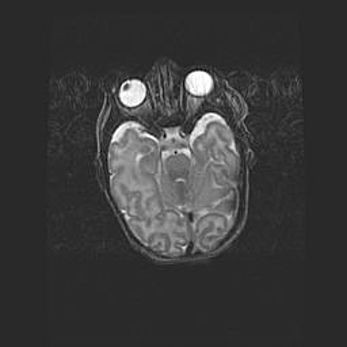

Сообщающаяся гидроцефалия. Кистозная энцефаломаляция головного мозга.

Возраст: 3 месяца 4 дня

Вес: 3100 г

Пол: женский

Окружность головы: 34 см

Срок гестации: 31 неделя

Кистозная энцефаломаляция головного мозга - одна из форм поражения головного мозга в детском возрасте. Характеризуется возникновением множественных и распространённых кист в коре, белом веществе и подкорковых образованиях головного мозга у плодов, новорождённых и детей раннего возраста. Развитие кистозной энцефаломаляции связано с внутриутробной асфиксией и гипотонией, родовой травмой, тромбозом синусов, пороками развития сосудов, инфекциями, сепсисом и другими причинами. Наиболее значимые инфекционные агенты: вирусы простого герпеса, цитомегалии, краснухи, токсоплазмы, энтеробактерии, золотистый стафилококк и другие.